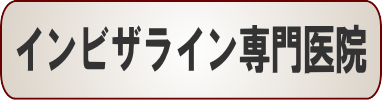

☆歯のデコボコ矯正症例(Y.I様 30歳 男性)

・きっかけ

上の前歯が1本が突き出していて、昔から気になっていました。

特にアメリカに留学した際、皆歯並びを気にしているせいか、みんなが綺麗な歯並びで余計気になるようになりました。

ただ矯正は高いというイメージがあり、行動に移せずにいましたが、たまたまインターネットで部分矯正を知り、値段的にも前歯だけ治せれば良いという、意識的にも自分にぴったりだと思い、今回矯正することにしました。

・感想

治療していただくことで綺麗な歯並びとなり、歯を出して笑うことが多くなりました。

担当の日高さんも分かりやすく説明して下さり、質問にも快く答えて下さり、安心して治療を受けることができました。

本当にありがとうございました。

他のスタッフさんも笑顔で対応や挨拶をして下さり、とても感じが良かったです。